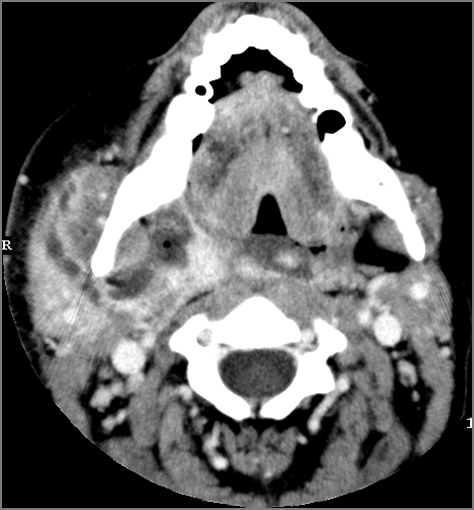

There is edema/abscess tonsillar or otherwise or likely suppurative retropharyngeal adenitis involving the oropharynx or adjacent deep tissue spaces.

There is edema/abscess within or surrounding the buccal space, masticator space, floor of the mouth, submandibular space or the adjacent superficial fascia or subcutaneous fat and skin.